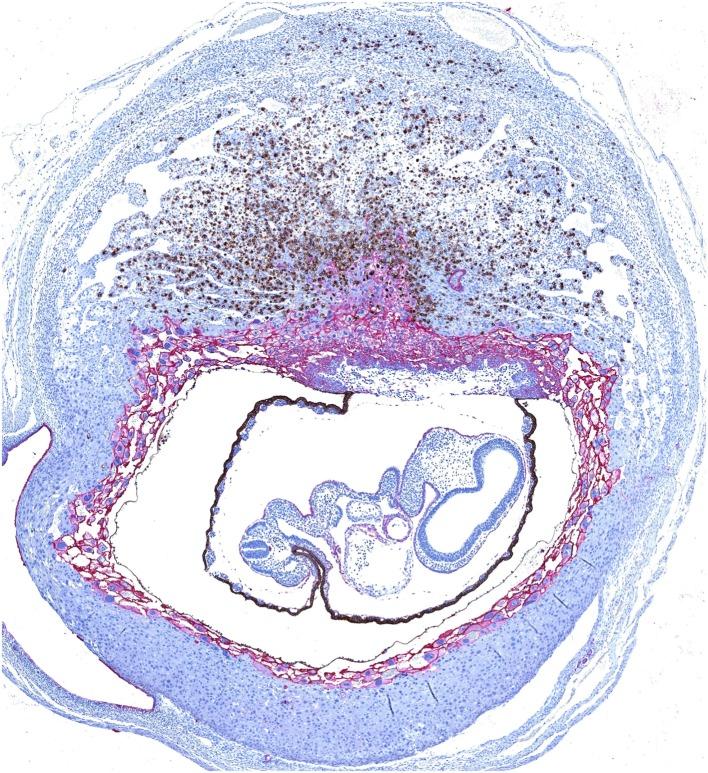

子宫自然杀伤细胞:人类和小鼠中的功能差异及其对妊娠的影响

Uterine Natural Killer Cells: Functional Distinctions and Influence on Pregnancy in Humans and Mice.

近年来,我们对自然杀伤(NK)细胞的发育和功能的理解有了显著进展。然而,子宫NK(uNK)细胞究竟如何发育和发挥功能仍不清楚。为了帮助刚开始研究组织NK细胞的研究人员,我们在这篇综述中总结了我们目前对uNK细胞发育和功能的认识,以及尚待阐明的问题。我们在固有淋巴细胞生物学的更广泛背景下,并参照外周NK细胞,比较和对比了人类和小鼠uNK细胞的生物学特性。我们还综述了uNK细胞在人类和小鼠妊娠中如何调节滋养层细胞浸润和子宫螺旋动脉重塑。